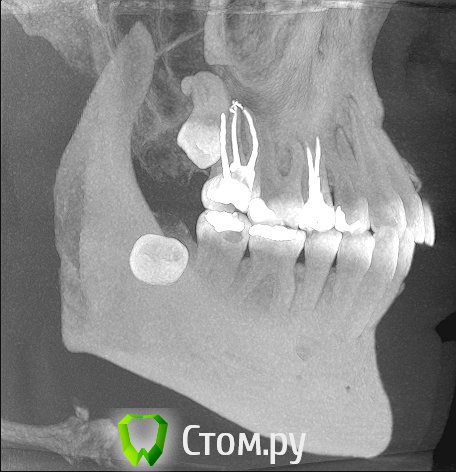

Сергей_vrn36 Опубликовано 3 марта, 2014 Поделиться Опубликовано 3 марта, 2014 (изменено) пару недель периодически ноет в районе 7-8 зубов (ну которые верхние, справа). плюс ко всему, когда ноют зубы закладывает нос. 8й зуб мудрости лезет уже второй год и думаю уже и не вылезет - на снимке видно, что он упирается в низ 7-го, находясь как бы между корнями (ну это я так снимки рассмотрел). в клиниках врачи говорят, что такие зубы удаляют в стационарах, т.к. он выходит почти наполовину в носовую пазуху. какие вобще прогнозы по поводу удаления этого зуба, чего мне следует начинать бояться? - корень там завитком, заходит в пазуху и мне кажется будет цепляться за дно при удалении. какова вероятность, что он (корень) останется в пазухе при удалении зуба и какая будет нужна операция(?), чтобы потом его оттуда достать?ps/ наверно надо было в другом разделе темку сделать. но я рад любому совету. Изменено 3 марта, 2014 пользователем Сергей_vrn36 Ссылка на комментарий